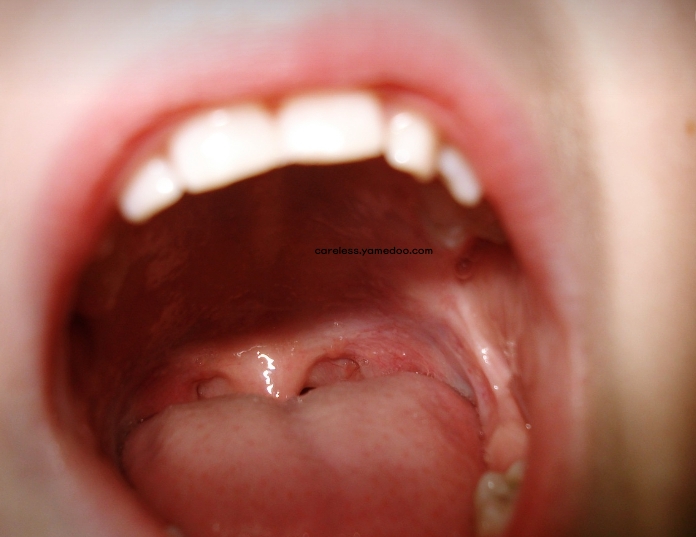

혓바늘이 돋는 이유

혀는 우리 몸의 건강 상태를 보여주는 중요한 지표 중 하나로, 혓바늘의 원인을 이해하고 적절히 관리하는 것이 중요합니다. 혓바늘이 돋는 8가지 주요 이유를 자세히 살펴보겠습니다.